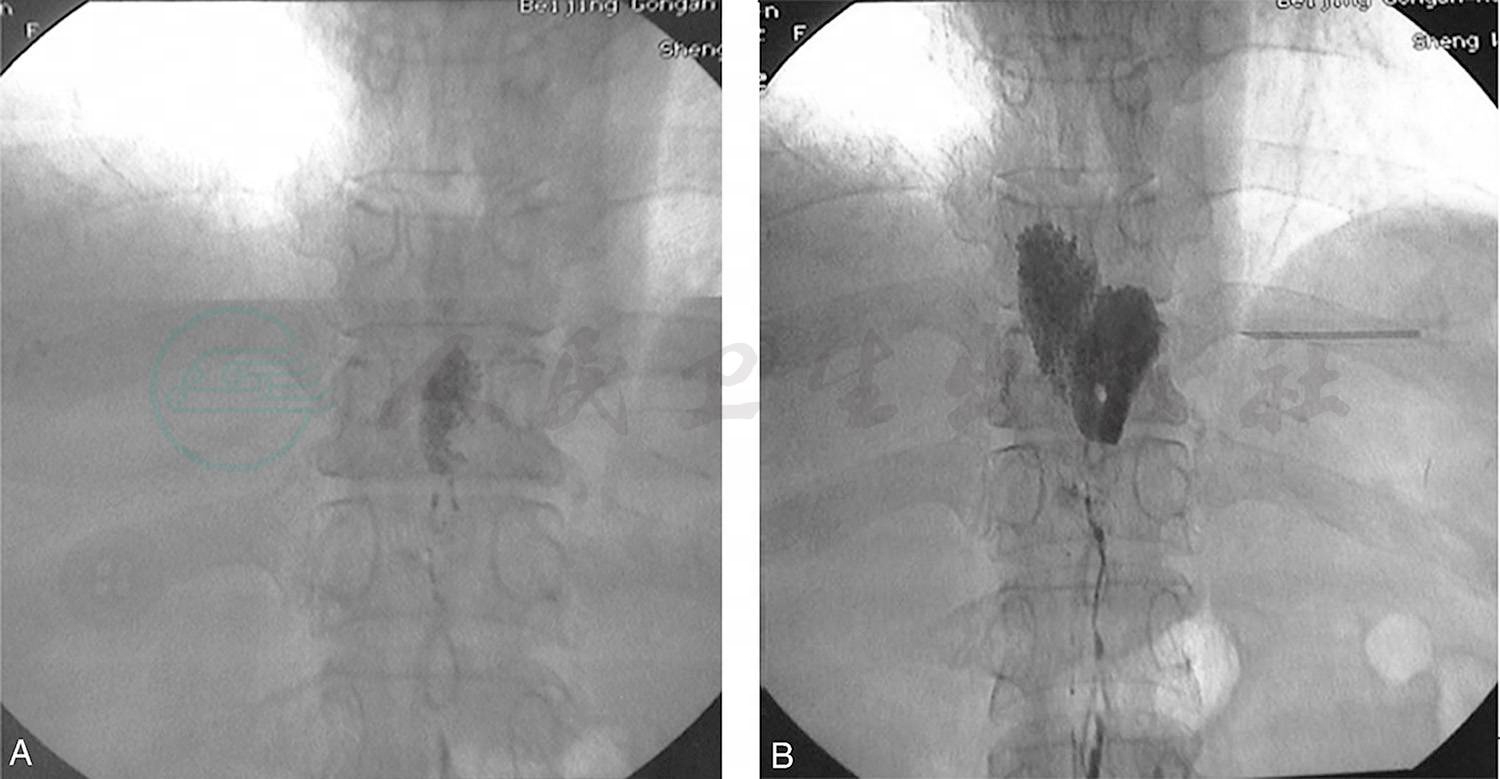

图2直接淋巴管造影显示不同时间所拍摄的乳糜池瘘的影像

图3直接淋巴管造影显示髂淋巴管瘘